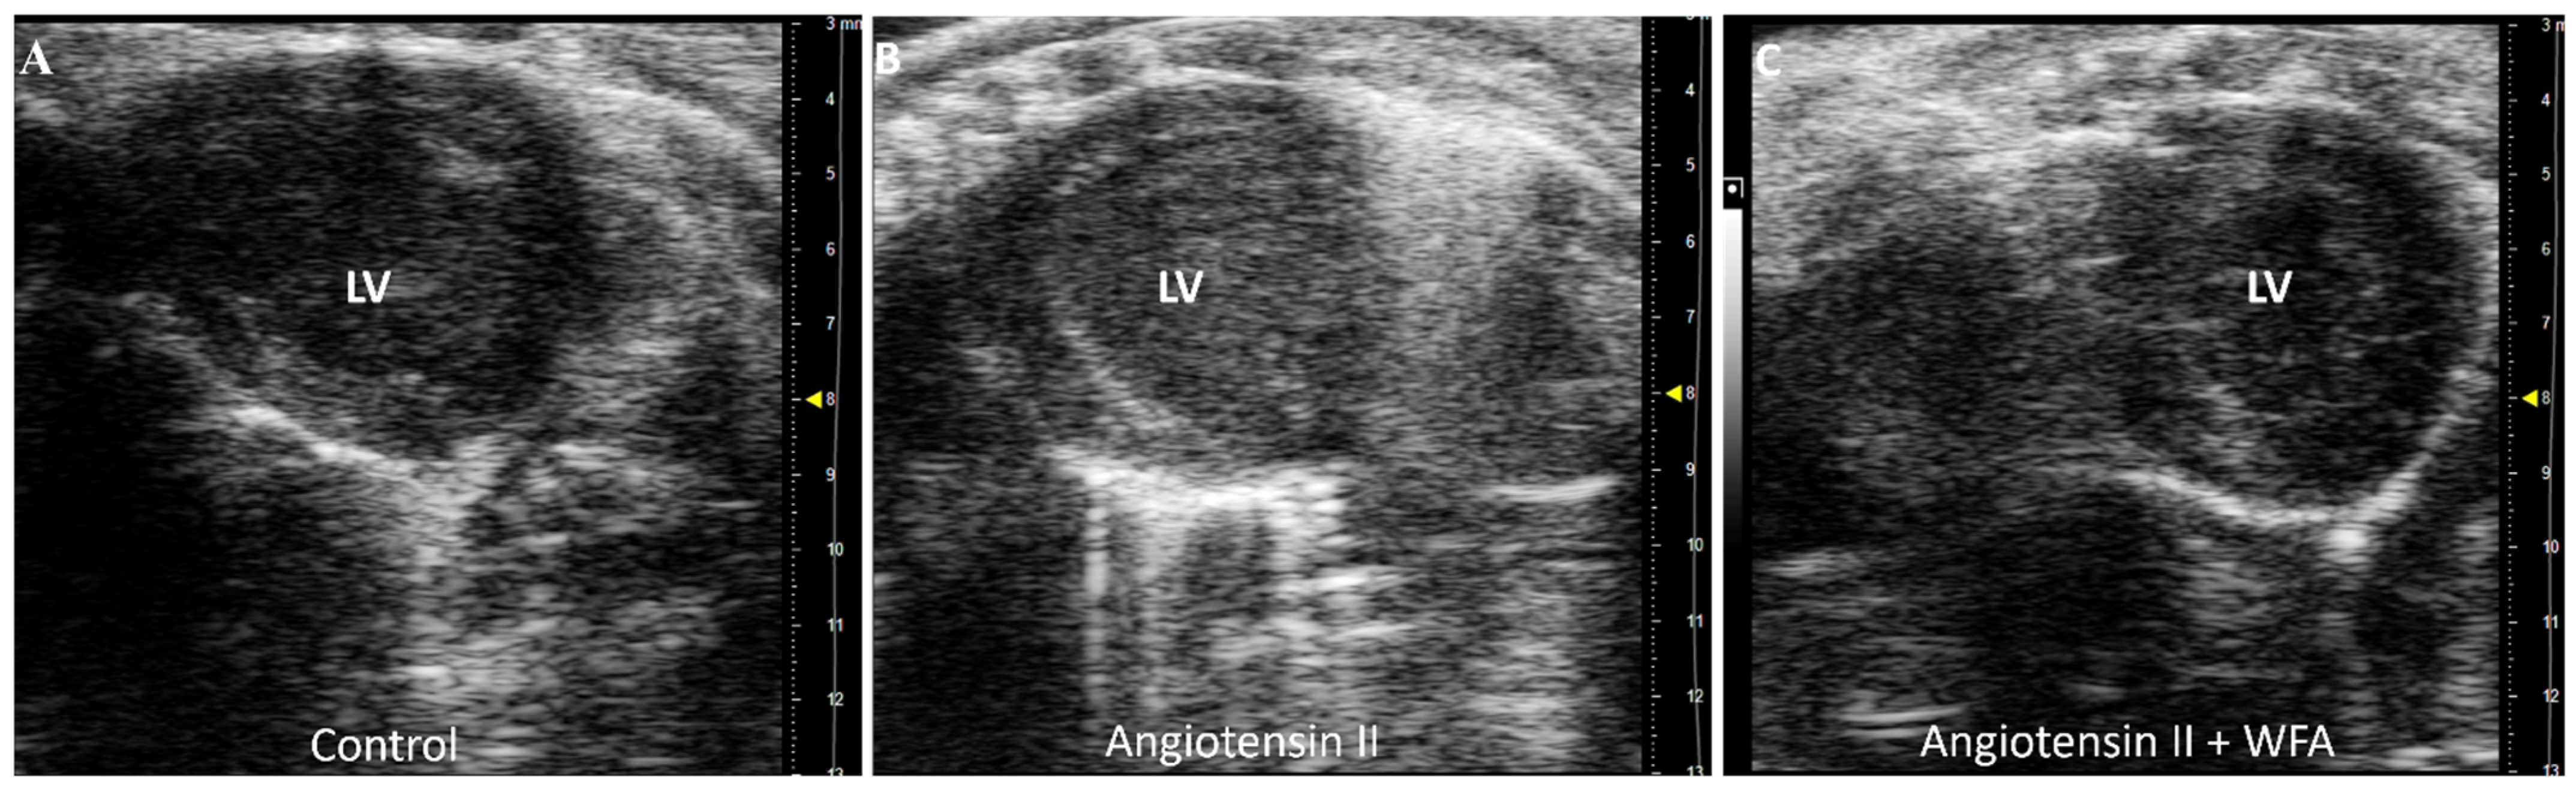

The scanning of the LV using echocardiography showed significant damage to LV, associated with the abnormal contractility of the LV in Ang II-infused mice compared to saline-infused mice. Treatment of mice infused with Ang II with WFA completely abrogated the damages and restored LV contractility to or above control levels (Figure 3, Supplementary Materials Video S1). These results suggest the induction of cardiac dysfunction by the continuous infusion of Ang II and its reversal by WFA. No difference in LV contractility was observed between the saline–vehicle and saline–WFA groups.

Figure 3.

Video 1. Effect of WFA on contractility of LV. WFA significantly increased and restored LV systolic function, as shown in the parasternal short-axis view of transthoracic echocardiography. (A) Control mice which showed normal LV systolic function; (B) Angiotensin II/vehicle mice which demonstrated reduced LV systolic function; and (C) WFA + Ang II mice which showed significantly increased LV systolic function, even higher than the control mice. No difference in LV systolic function between saline-infused and saline–WFA groups. LV = left ventricle. Video S1 included in the Supplementary Materials. Dimension = 1 mm.

The first report of cardiac changes in cancer-induced cachexia in mice was reported by Tian et al., in 2010 [39], where the heart showed dysfunction on day 14 after tumor inoculation, reflected by reduced fractional shortening in vivo by echocardiography. At necropsy (on day 17), the hearts of the tumor-bearing mice group displayed significant fibrosis, and further analysis by transmission electron microscopy revealed a disrupted myocardial ultrastructure. The gene expression of troponin I, a regulator of cardiac muscle contraction, was reduced along with mRNA, and protein levels of MHCα decreased and MHCβ increased. These changes were recaptured in our ovarian-cancer-bearing mice [14]. Therefore, cardiac dysfunction in mice with tumor-induced cachexia was associated with an altered composition of contractile proteins of cardiac muscle, increased myocardial fibrosis, and a disrupted cardiac muscle structure, which are universal features of cardiac cachexia rather than a type of tumor-dependent phenomenon. In the present study with the continual infusion of Ang II for 4 weeks, the general features of cardiac cachexia were determined to show a significant decrease in cardiac functions (Figure 1, Figure 2 and Figure 3), structural remodeling, including increased MHCβ mRNA expression levels (Figure 4), and myocardial fibrosis (Figure 6), confirming the success of this model and mimicking the cancer-induced cardiac cachexia model.